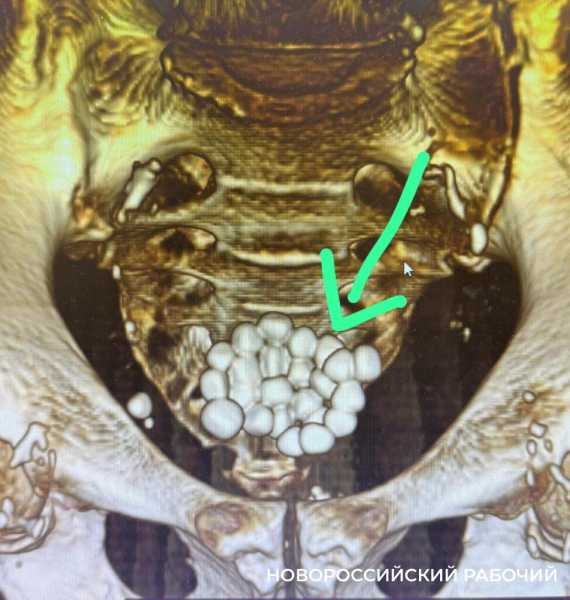

Но у этого больного проявились осложнения — в мочевом пузыре образовалось 24 камня диаметром от 1,0 до 1,5 см. Чтобы спасти пациента, ему одномоментно выполнили 2 операции. Не только удалили все камни, но и провели трансуретальную резекцию простаты.